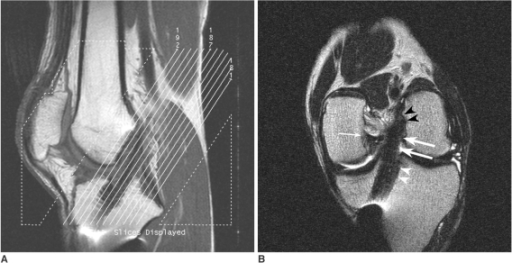

Coronal Oblique ACL assessment.

Ref: Grading anterior cruciate ligament graft injury after ligament reconstruction surgery: diagnostic efficacy of oblique coronal MR imaging of the knee. Moon SG, Hong SH, Choi JY, Jun WS, Choi JA, Park EA, Kang HS, Kwon JW - Korean J Radiol (2008 Mar-Apr)

ACL graft – Check

Check tibial tunnel angle and Blumensaat’s line

Graft patency/ laxity